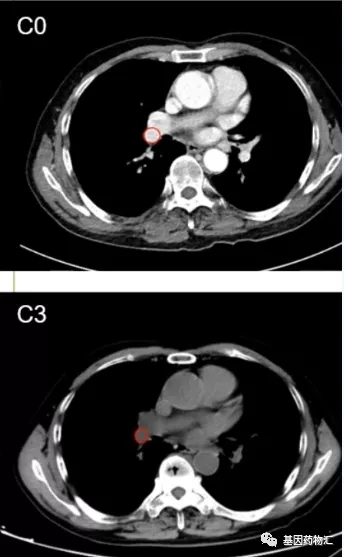

Ⅰ期试验案例分享:ROS1融合突变患者持续治疗超过11个月

患者男,36岁,右中下肺腺癌伴多发转移,T4N3M1c,Ⅳb期;基础情况:ECOG评分1分,伴随扁桃体肿大、咳嗽、咳痰、气促、屈光不正,ROS1融合阳性。

患者于2019年9月6日起接受TQ-B3101治疗,剂量为300 mg bid,达到部分缓解,目前仍在接受治疗,治疗持续超过11个月。

C1周期末时,患者右肺门肿块消失